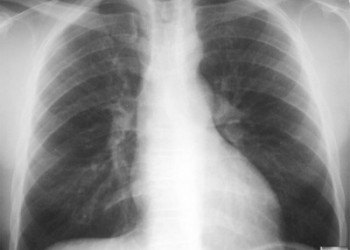

Pacient? în vârst? de 11 ani cu boal? cardiac? congenital? este supus? unei interven?ii chirurgicale de corectare a defectului cardiac.

Preoperator, aspectul radiologic arată ca în imagine. Postoperator dezvoltă durere abdominală, meteorism și vărsături, iar la examenul clinic se remarcă zgomote intestinale reduse. Chirurgul ridică suspiciunea unei ischemii intestinale ca o complicație a chirurgiei cardiace. Care dintre următoarele este cel mai probabil defectul cardiac al pacientei?

Foto: learningradiology.com